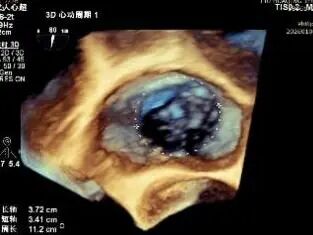

Tricuspid valve: Type IIIb quadricuspid malformation with insufficiency, secondary severe regurgitation (4+), mild annular dilatation (mean diameter 40 mm), mean vena contracta 10 mm. Regurgitant orifices are located at anteroseptal, central, and posteroseptal regions, with marked enlargement of the right atrium and right ventricle.

CTA: 31% systole: perimeter 135 mm, area 1373 mm²; 75% diastole: perimeter 146 mm, area 1597 mm².。

Annuloplasty Effect: The tricuspid valve annulus area was reduced from 9.96 cm² to 4.6 cm², representing a 53% decrease in annulus area.

Preoperative regurgitation (severe)

Postoperative regurgitation (trivial)

Surgical Outcome: Severe tricuspid regurgitation (4+) was reduced to mild tricuspid regurgitation (1+).